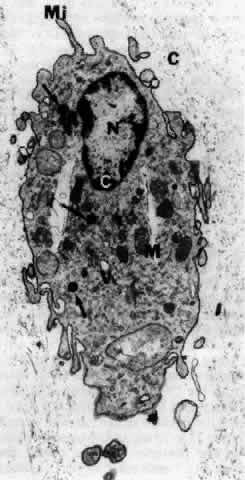

These mononuclear cells are embedded in the vitreous cortex (see Figs. 5, 13, AND 16), widely spread apart in a single layer situated 20 to 50 μm from the internal limiting lamina of the retina posteriorly and the basal lamina of the ciliary epithelium at the pars plana and vitreous base. Quantitative studies of cell density in the bovine160 and rabbit161 vitreous found the highest density of hyalocytes in the region of the vitreous base, followed next by the posterior pole, with the lowest density at the equator. As shown in Figure 17, hyalocytes are oval or spindle shaped, 10 to 15 μm in diameter, and contain a lobulated nucleus, a well-developed Golgi complex, smooth and rough endoplasmic reticula, and many large periodic acid-Schiff-positive lysosomal granules and phagosomes.50,162Hogan and colleagues163 described that the posterior hyalocytes are flattened and spindle shaped, whereas anterior hyalocytes are larger, rounder, and at times star shaped. Saga and associates164 have described that different ultrastructural features can be present in different individual cells of the hyalocyte population in an eye. Whether this relates to different origins for the different cells or different states of cell metabolism or activity is not clear.

Fig. 17. Ultrastructure of human hyalocytes. A mononuclear cell is seen embedded within the dense collagen fibril (black C) network of the vitreous cortex. There is a lobulated nucleus (N) with dense marginal chromatin (white C). In the cytoplasm there are mitochondria (M), dense granules (arrows), vacuoles (V), and microvilli (Mi) (×1670). (Courtesy of JL Craft and DM Albert, Harvard Medical School, Boston; Sebag J: The Vitreous--Structure, Function and Pathobiology. New York, Springer-Verlag, 1989)